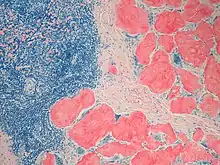

Diagnosis of amyloidosis generally requires tissue biopsy. The biopsy is assessed for evidence of characteristic amyloid deposits. The tissue is treated with various stains. The most useful stain in the diagnosis of amyloid is Congo red, which, combined with polarized light, makes the amyloid proteins appear apple-green on microscopy. Also, thioflavin T stain may be used.[11] A number of imaging techniques such as a DPD scan or SAP scan are also in use.[12]

Tissue can come from any involved organ, but in systemic disease the first-line site of the biopsy is subcutaneous abdominal fat, known as a "fat pad biopsy", due to its ease of acquisition versus biopsy of the rectum, salivary gland or internal organs. An abdominal fat biopsy is not completely sensitive, and sometimes, biopsy of an involved organ (such as the kidney) is required to achieve a diagnosis.[11] For example, in AL amyloidosis only 85% of people will have a positive fatpad biopsy using Congo red stain.[6] By comparison, rectal biopsy has sensitivity of 74–94%.[7]

Cardiac amyloidosis. H&E stain. Micrograph showing amyloid deposition (red fluffy material) in the heart (cardiac amyloidosis). Congo red stain.

Micrograph showing amyloid deposition (red fluffy material) in the heart (cardiac amyloidosis). Congo red stain.